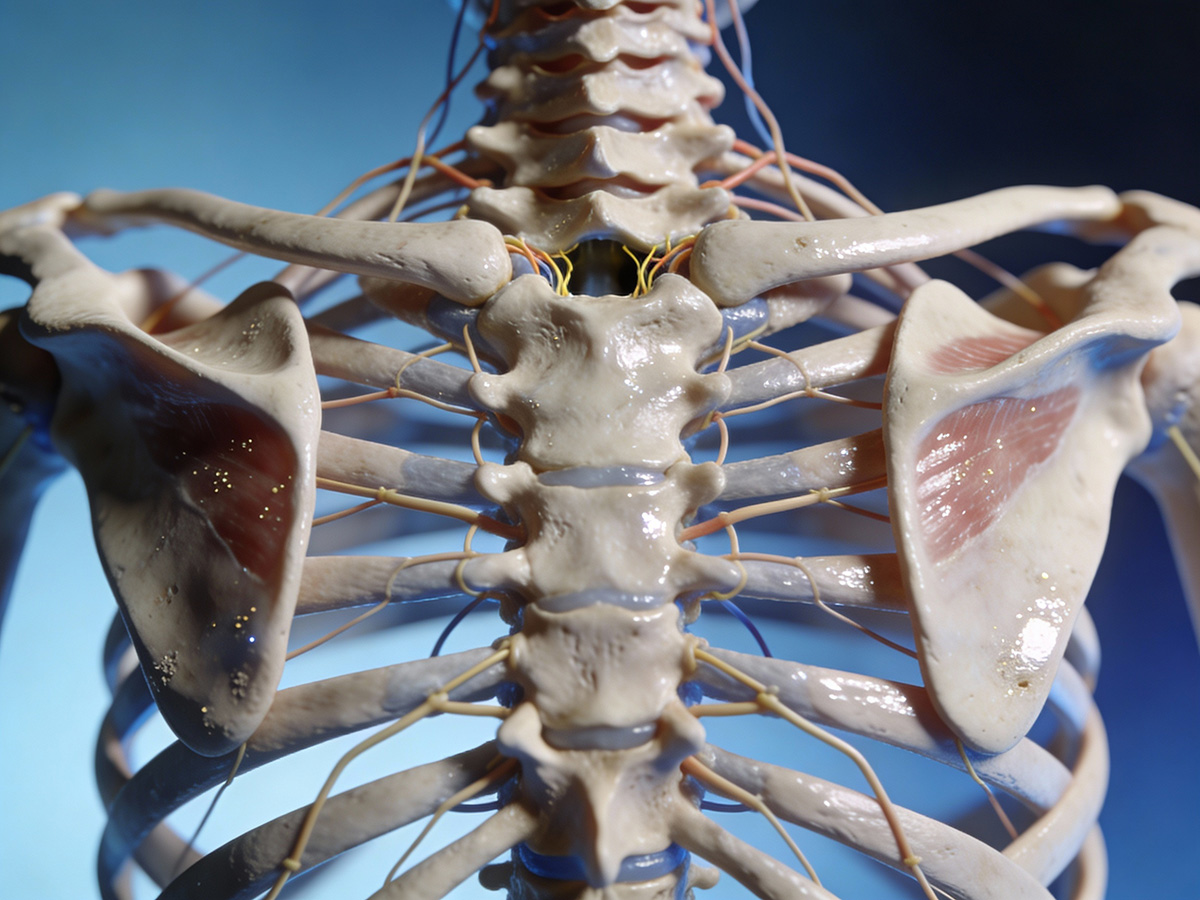

Wissenschafts- & Forschungskommunikation

Wir machen medizinische und wissenschaftliche Inhalte sichtbar – für Fachkreise, Entscheidungsträger und Öffentlichkeit.

Wir schaffen Visuals, die fachlich und visuell überzeugen – für Forschung, Ausbildung und Healthcare-Kommunikation

In unserer Galerie zeigen wir exemplarisch KI-basierte Bild- und Bewegtbildwelten aus verschiedenen Bereichen. Filtern Sie nach Themen – und sehen Sie, wie wir komplexe Inhalte in klare Visuals übersetzt haben.

Jedes Motiv ist ein Beispiel dafür, wie wirkungsstark KI-Bildproduktion und KI-Motion gezielt für Healthcare- und Wissenschaftskommunikation sein können.